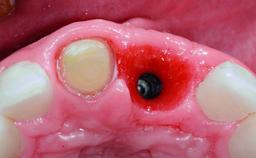

A 32-year-old female Caucasian patient with a compromised maxillary right central incisor was referred to us by a general dentist. Her chief complaints were discomfort and mobility of tooth 11 with unsatisfactory esthetics due to discoloration. The patient reported a previous trauma, some years earlier, as the origin of pathology on the afflicted tooth. Anamnesis was negative for any other dental or periodontal pathology in the remaining dentition. The patient did not take any medication and reported to be a light smoker (5–10 cigs/day). She had high esthetic expectations of her treatment. The extraoral examination revealed a high smile line with full exposure of her maxillary teeth and surrounding soft tissue in the area between the second premolars.